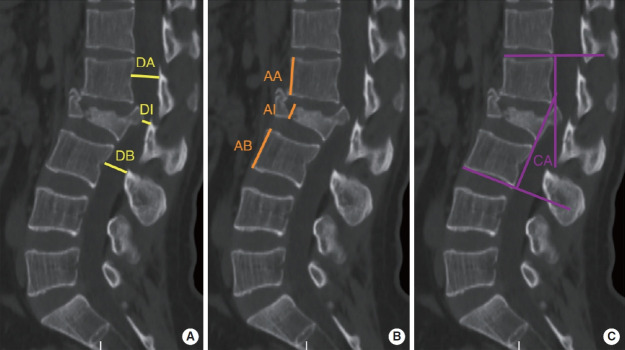

Results: Among the 231 patients who were followed up for more than 2 years, 107 were in the EMIS cohort and 124 were in the OS cohort. Compared with the OS cohort, the EMIS cohort had longer operative time (p<0.05), but the intraoperative blood loss, incision length and hospital stay were significantly reduced (p<0.05). At both postoperative and final follow-up assessments, the EMIS cohort demonstrated significantly better visual analogue scale and Oswestry Disability Index outcomes compared to the OS cohort (p<0.05). Both cohorts maintained similar correction of spinal canal erosion rate, percentage of anterior vertebral height and sagittal Cobb angle after surgery and at the last follow-up (p>0.05). According to American Spinal Injury Association classification, the 2 cohorts had similar neurological recovery at the last follow-up (p>0.05).